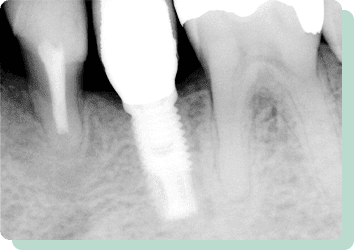

この患者様は右下に1本永久歯の先天性欠如がありました。ブリッジ・入れ歯・インプラント、いずれの処置法も可能ですが、前後の歯に負担をかけたくない、しっかりと左右で噛みたいという希望であったため、インプラント治療にて対応しました。

リスク:疼痛・咬合時痛・冷水痛・出血・インプラント手術による歯ぐきなどの損傷・インプラント周囲炎など

費用:インプラント治療1本あたり440,000円